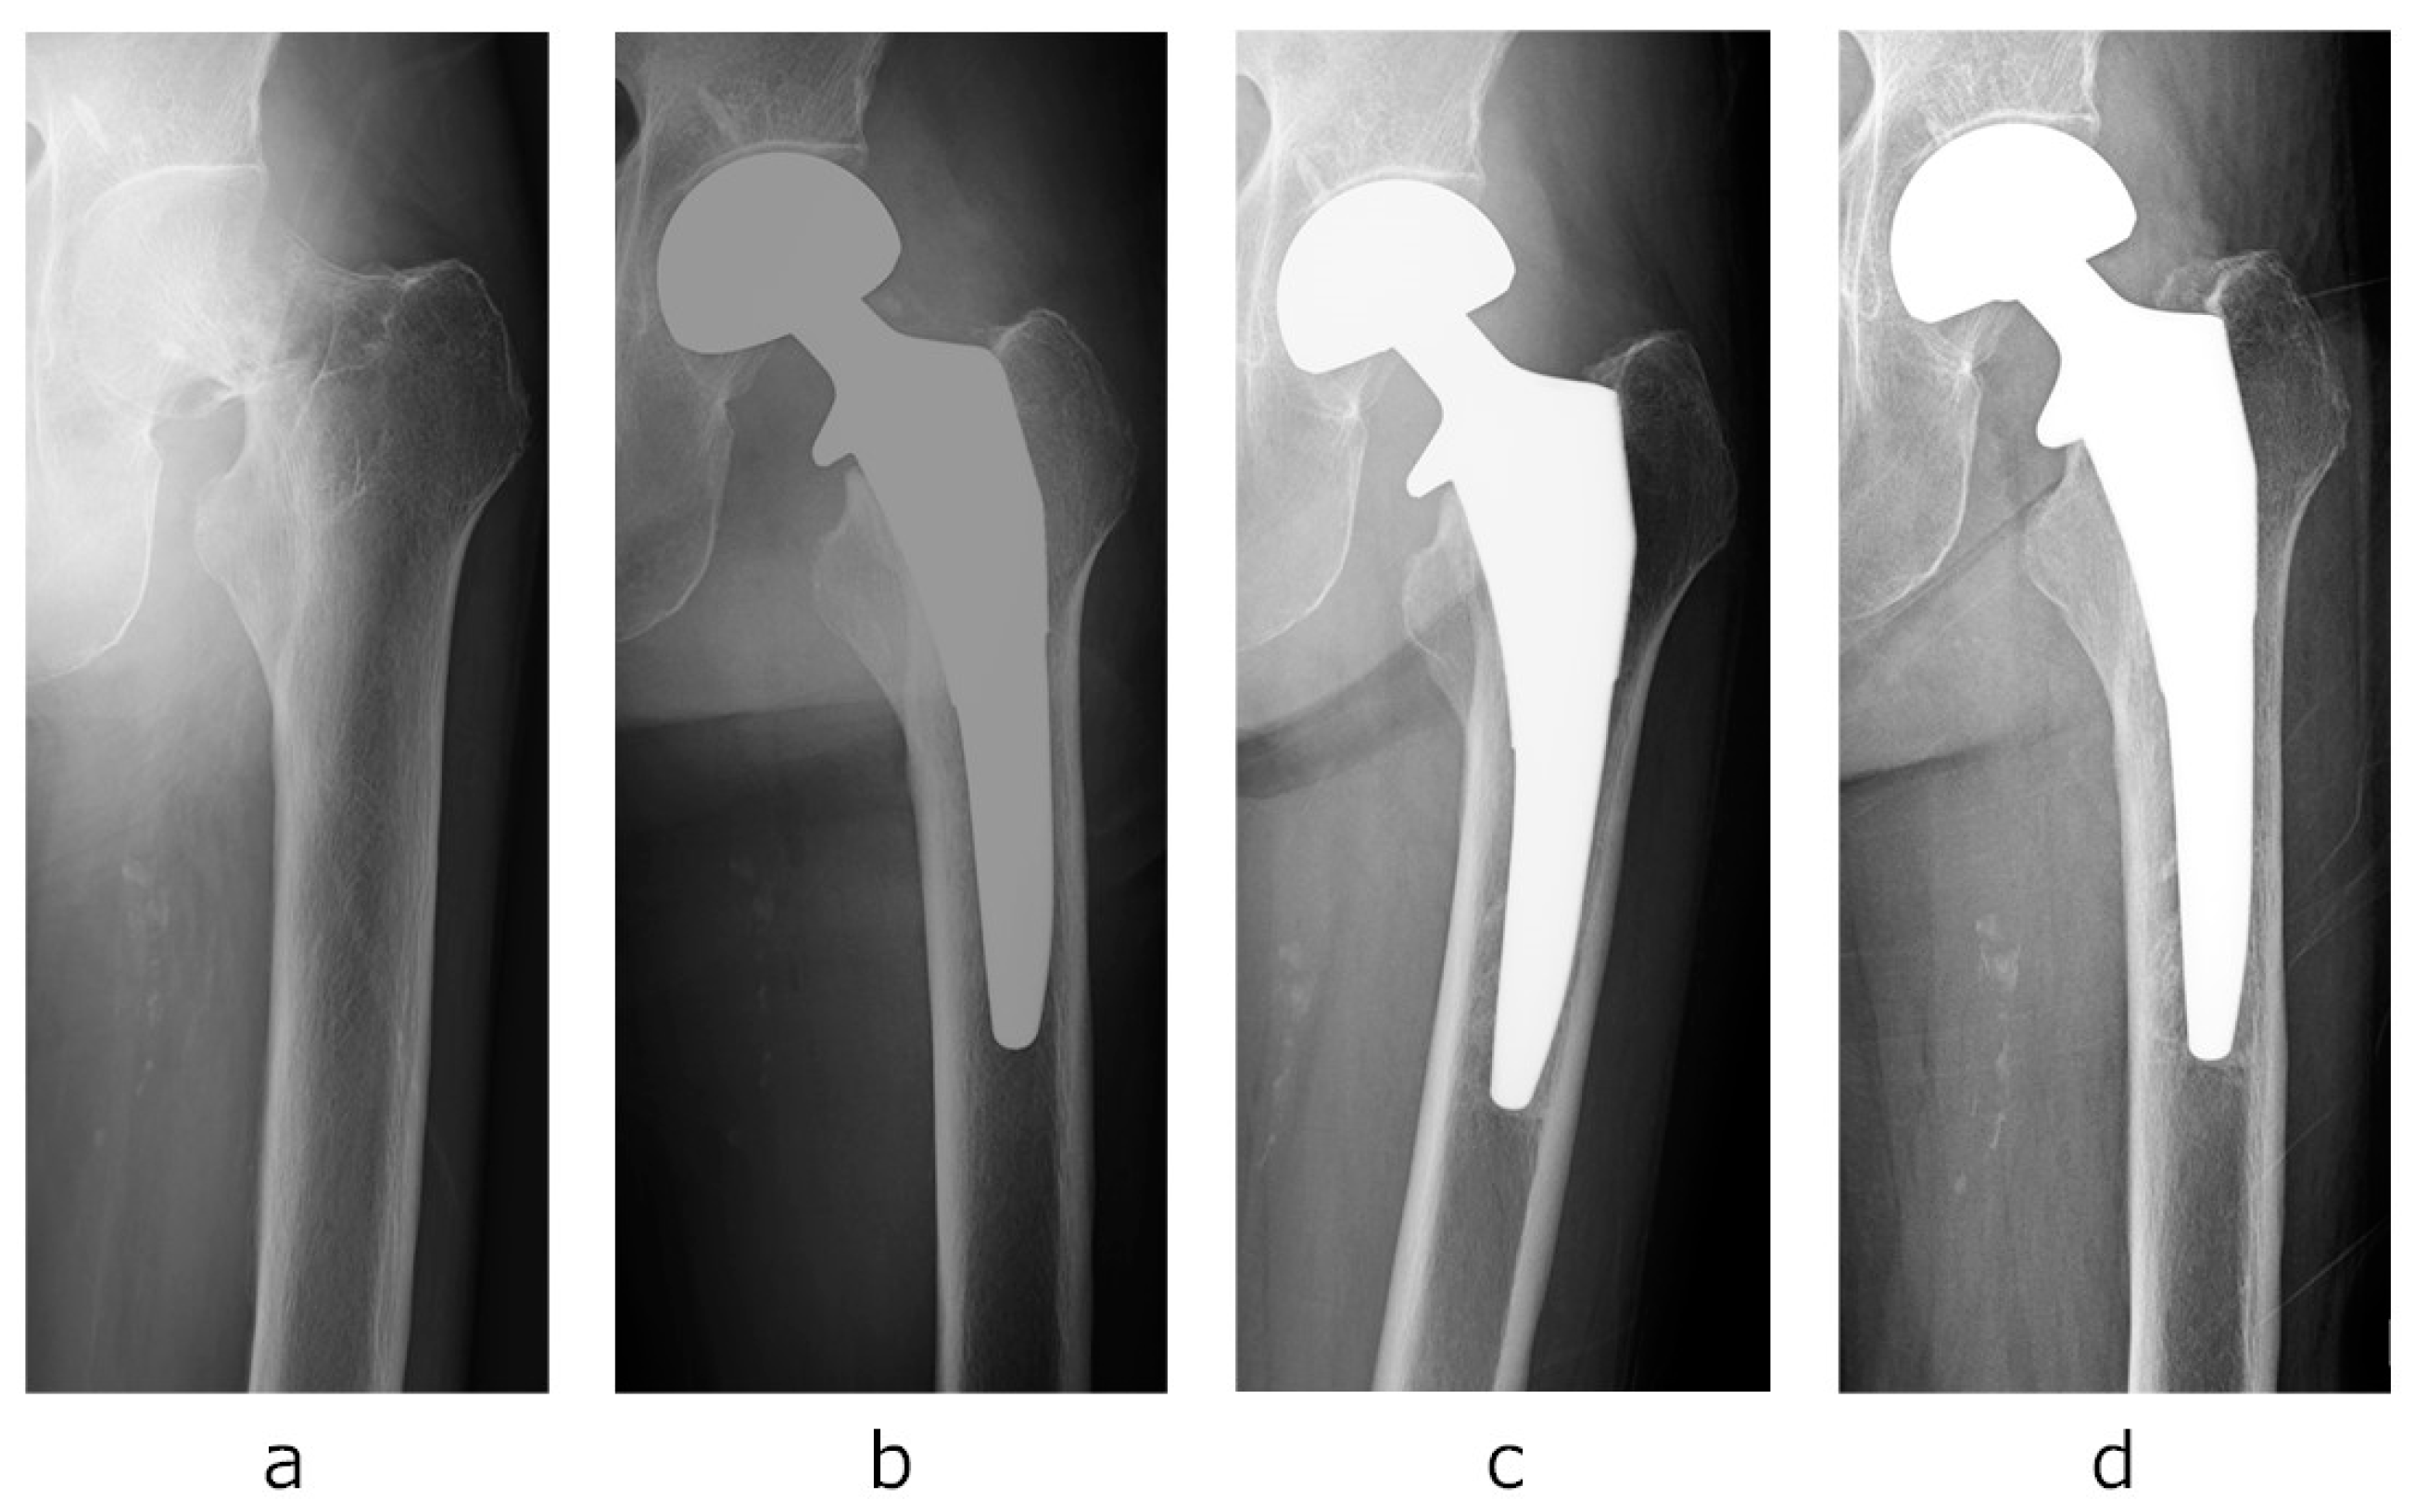

- Case presentation